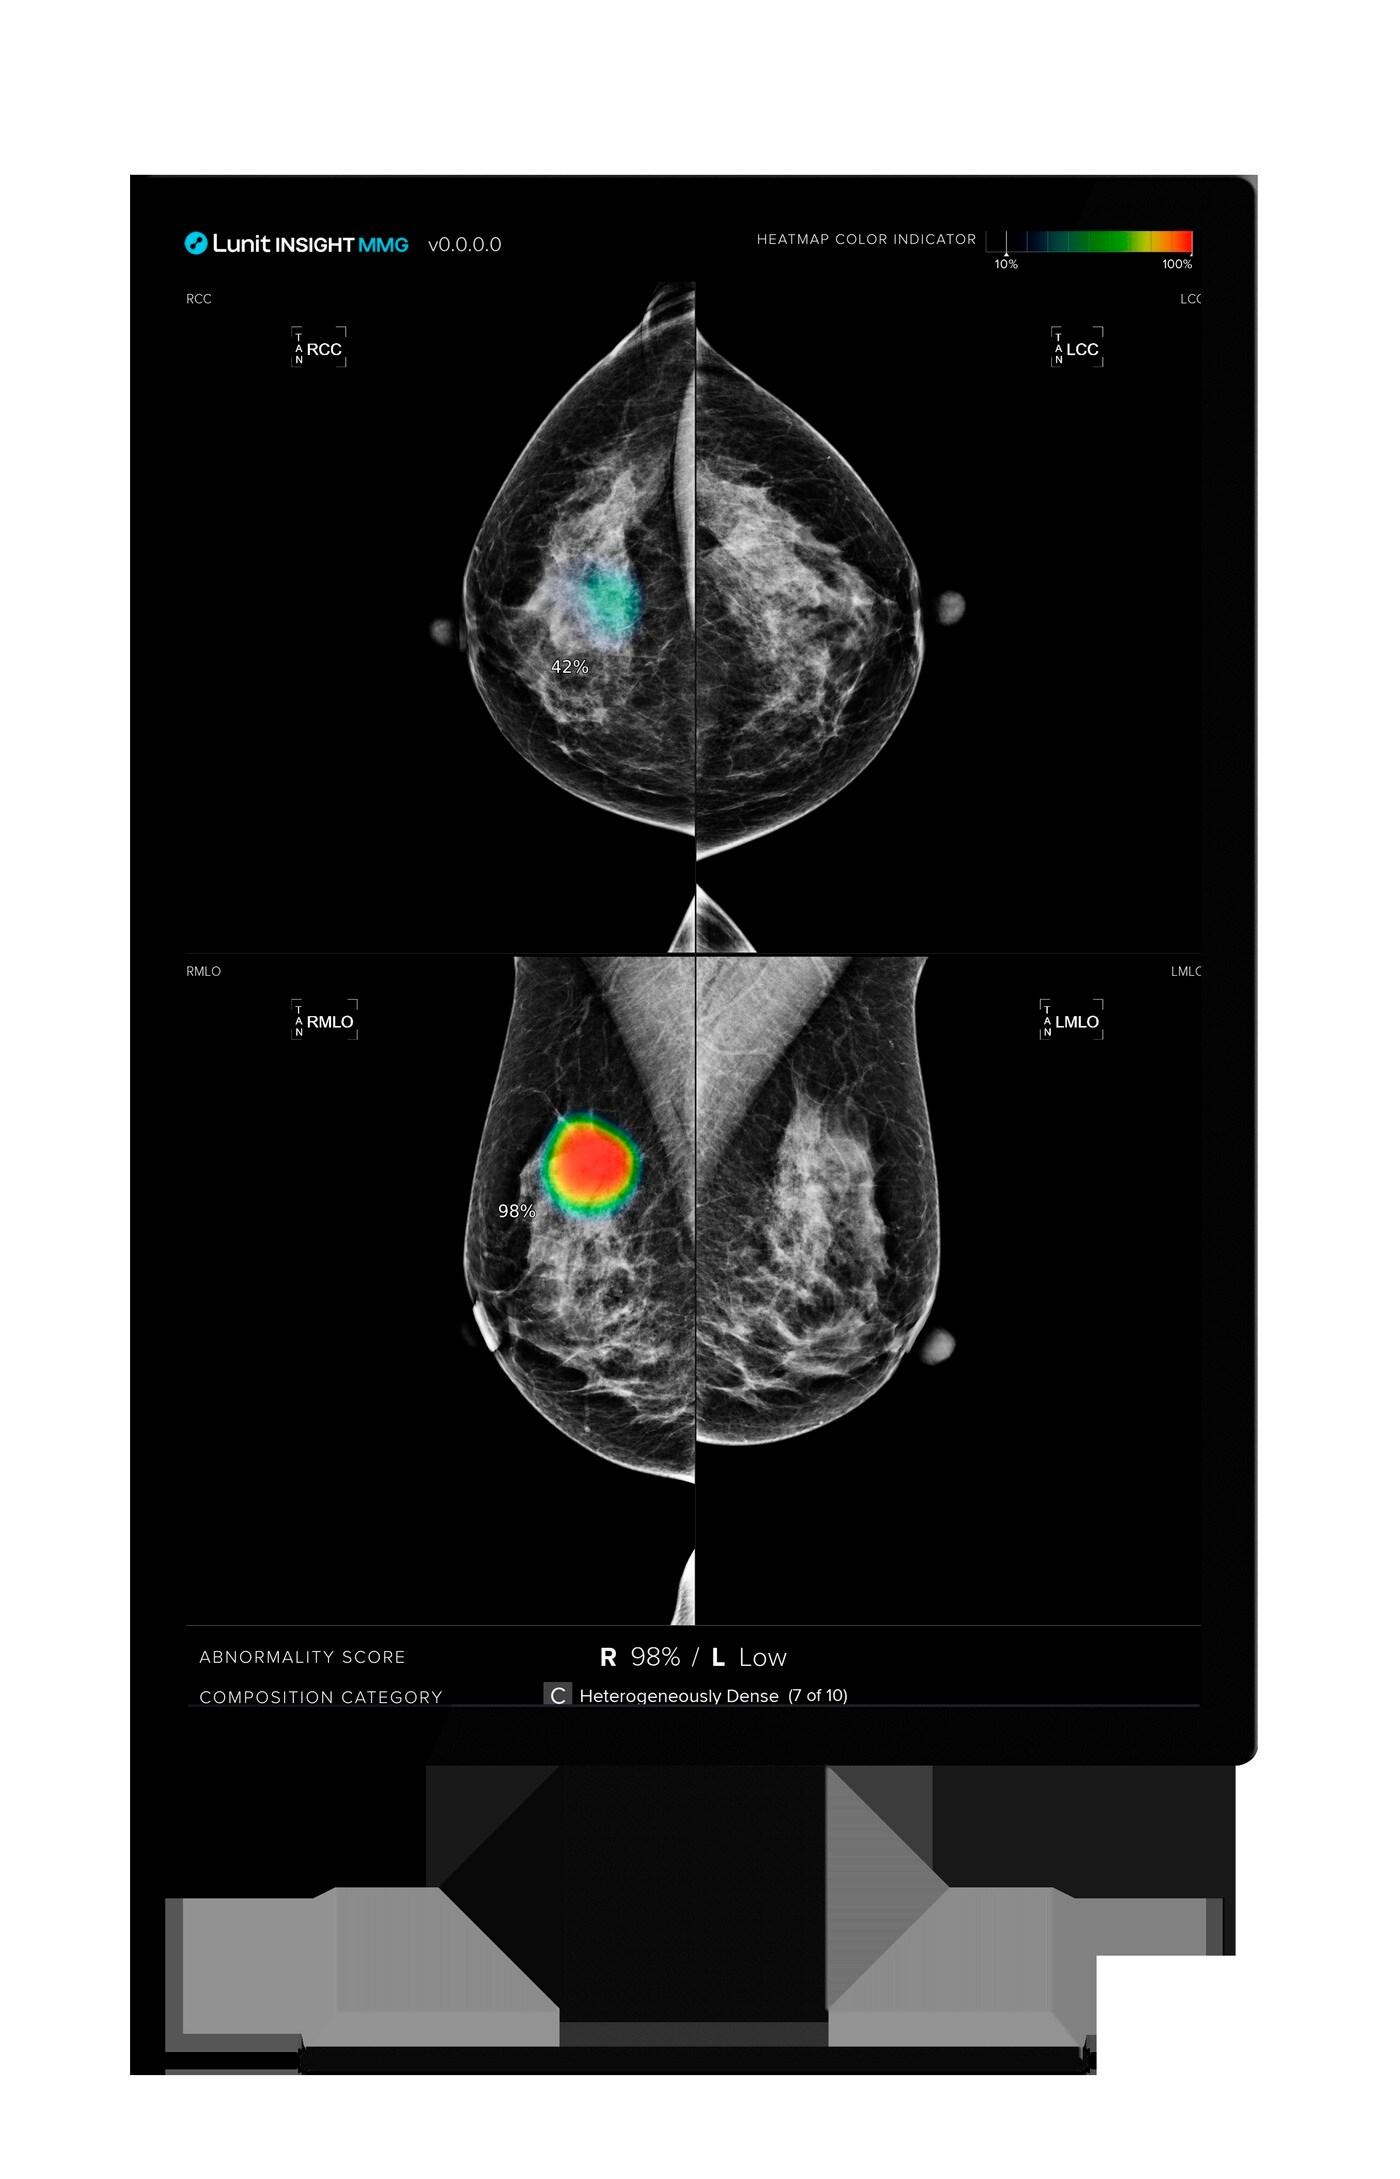

동국생명과학, 대전성모병원에 루닛 AI 유방암 진단 'MMG' 공급